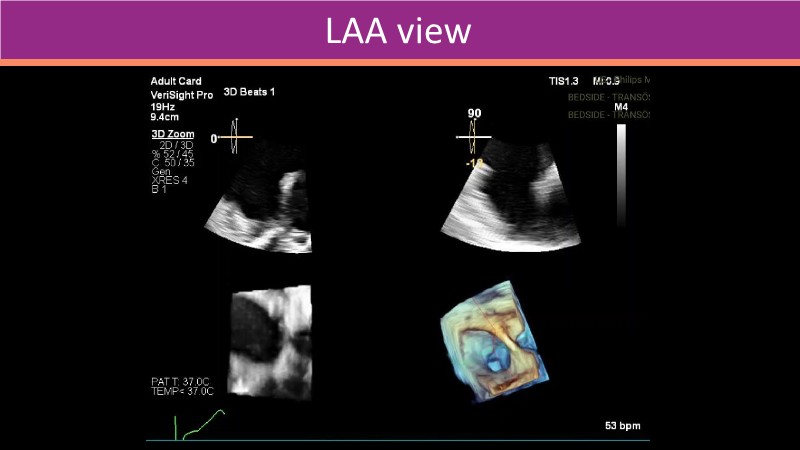

This PCR London Valves 2025 session explores how 3D TEE, 3D intracardiac echocardiography (ICE), and DeviceGuide technology sharpen procedural accuracy, strengthen operator confidence, and streamline decision-making in real time.

The session also includes detailed case analyses—such as Mitral TEER and LAA closure—and dual perspectives from both proceduralists and imagers.